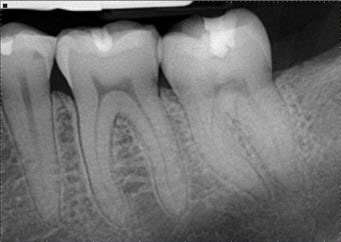

Root Canal Treatment

Many of you may carry a misconception about root canal treatment that it is a painful procedure, however, you will fret less once you understand why root canals are done. The removal of infected soft tissue within a tooth, and replacing it with a new artificial inert filling like material is a standard root canal procedure.

If the following problems persist, you are in ardent need for a root canal treatment.

- constant ache in tooth

- Tooth decay or extensive cavities

- Teeth darkening, possibly after a serious injury or trauma

- Gum swelling near tooth

- Sensitive gums or teeth

- Tooth fractureh